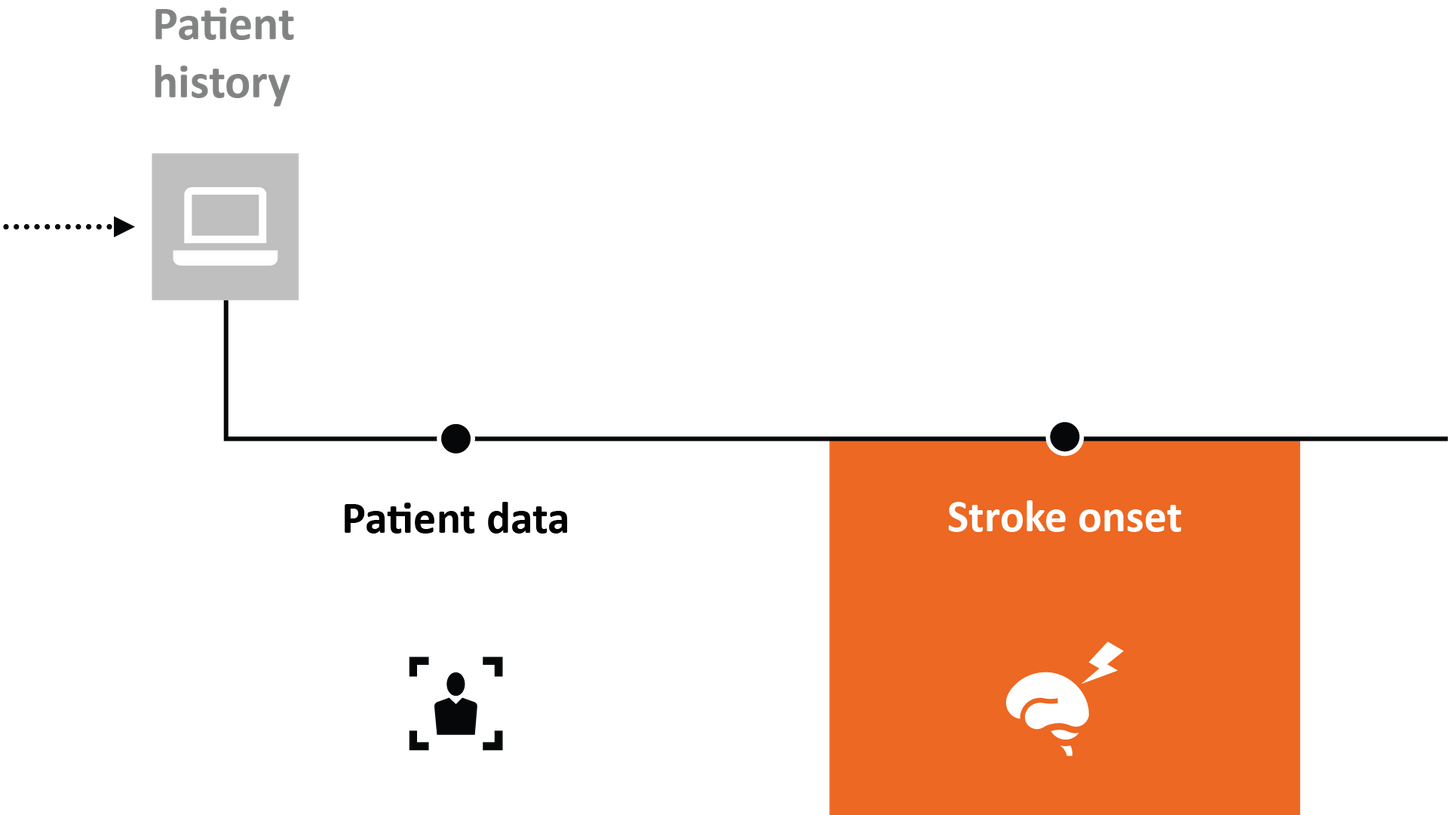

For stroke patients, time is of the essence. Every minute saved can positively impact patient outcomes.

That’s why it’s key to save time along the entire stroke pathway – from the onset of stroke to treatment and follow-up.

Stroke solutions

As your partner in stroke management, we keep you ahead of your time. Our advanced technologies let you speed up stroke care and transform care delivery along the entire pathway – from stroke screening and pre-hospital diagnosis and care to in-hospital diagnosis and treatment and (secondary) stroke prevention to follow-up imaging. Explore our offerings for stroke care!